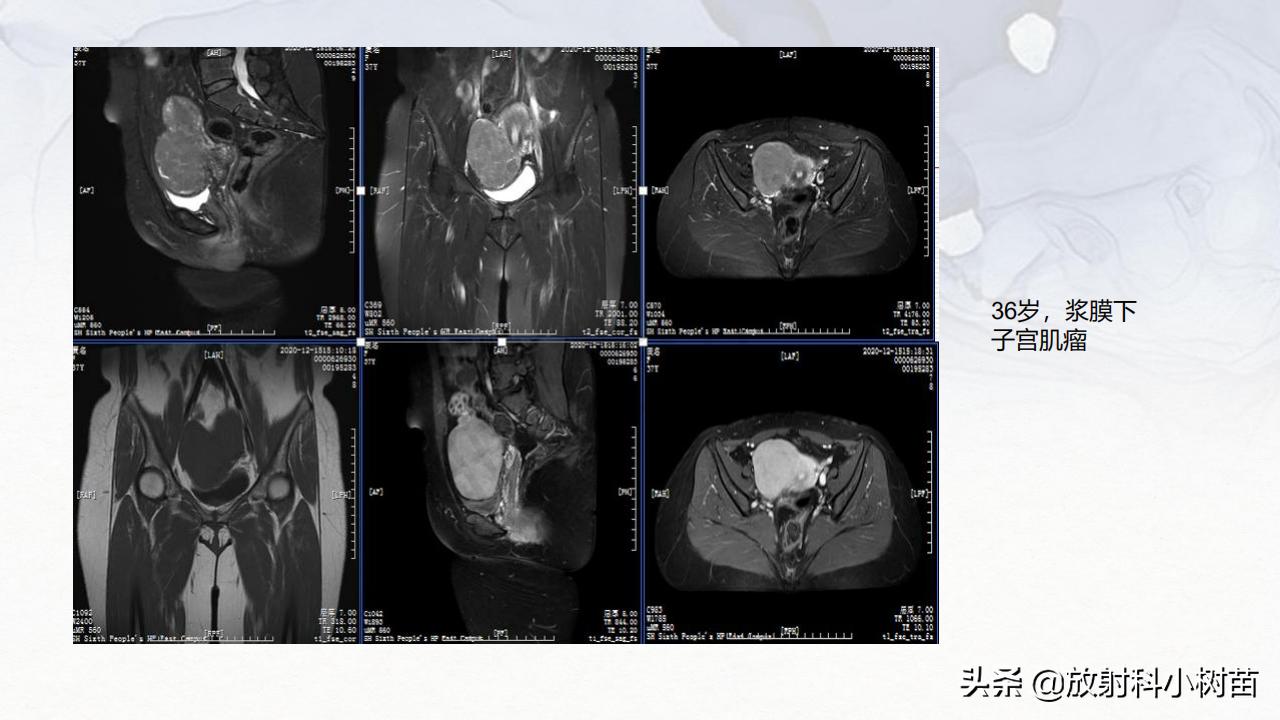

子宫体:肌层?(腺肌症,肌瘤,肉瘤),内膜?(增生,息肉、内膜癌)

卵巢:囊性?(单囊?(生理性囊肿,浆液性囊腺瘤、巧克力囊肿),多囊?(囊腺瘤,囊腺癌,巧克力囊肿),囊实性?(黏液性囊腺瘤,囊腺癌,癌畸癌),实性?